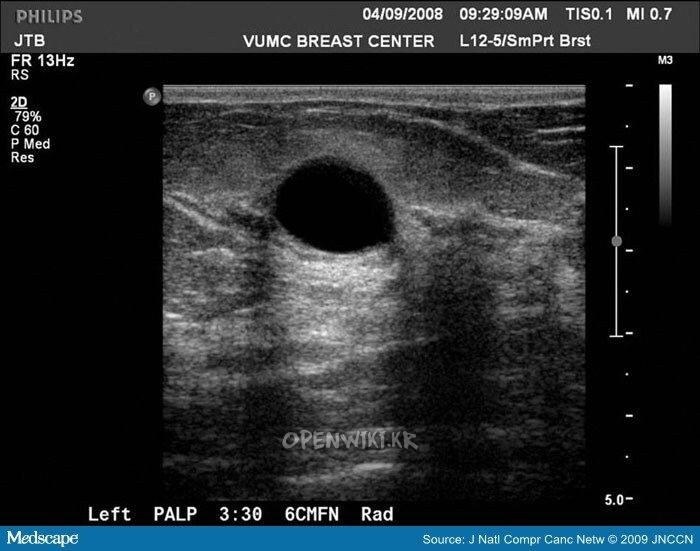

단순낭종

- 무에코

- 균질함

- 둥글거나 타원형

- 주위와 구분되는 명확한 경계

- 후방음영증가

- 누를때 형태가 변하고, 통증이 없다.

- 도플러검사에서 혈관 없슴